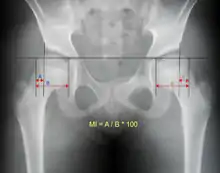

Reimer's migration index can be used to indicate hip dislocation. The migration index (MI) is normally less than 33%.[23]

An anterior-posterior (AP) X-ray of the pelvis and a cross-table lateral X-ray[24] of the effected hip are ordered for diagnosis.[4][5][16] The size of the head of the femur is then compared across both sides of the pelvis. The affected femoral head will appear larger if the dislocation is anterior, and smaller if posterior.[7] A CT scan may also be ordered to clarify the fracture pattern.[20]